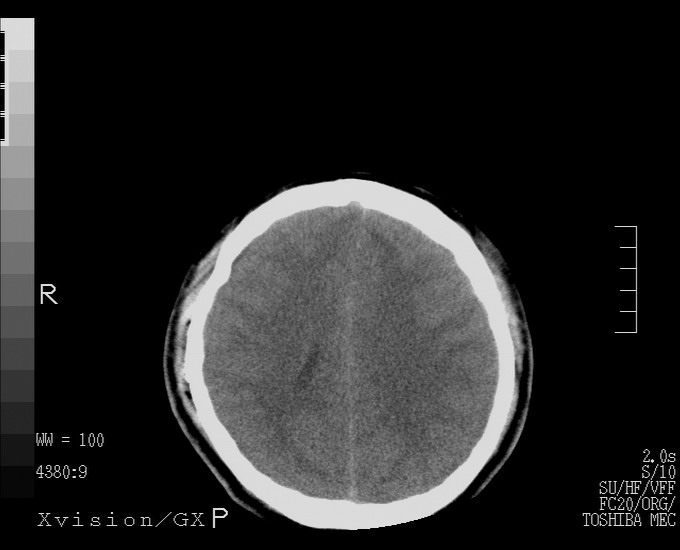

以下是引用随光逐影在2010-4-11 11:00:00的发言:[br]1)左侧额颞顶部硬膜下血肿。2)蛛网膜下腔出血。3)右侧颞顶部颅骨线形骨折。[br][br]20小时后复查:左侧额颞叶脑挫裂伤;左侧额颞顶部硬膜下血肿及蛛网膜下腔出血有吸收表现;右侧颞顶部颅骨线形骨折。[br]